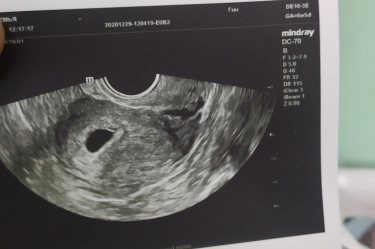

Девочки ,внутренний размер плодного яйца 11 мм ,мешочка желточного и эмбриона пока не видно ,срок ставят 3 н 3 д эмбриональный ,было ли у кого-то ,что не видели сразу ? Как потом ? Все нашли ?

В 5 недель по М было видно только плодное яйцо) подождите немножко и все покажется)

3 недели очень мало для обнаружения эмбриона, подождите немножко